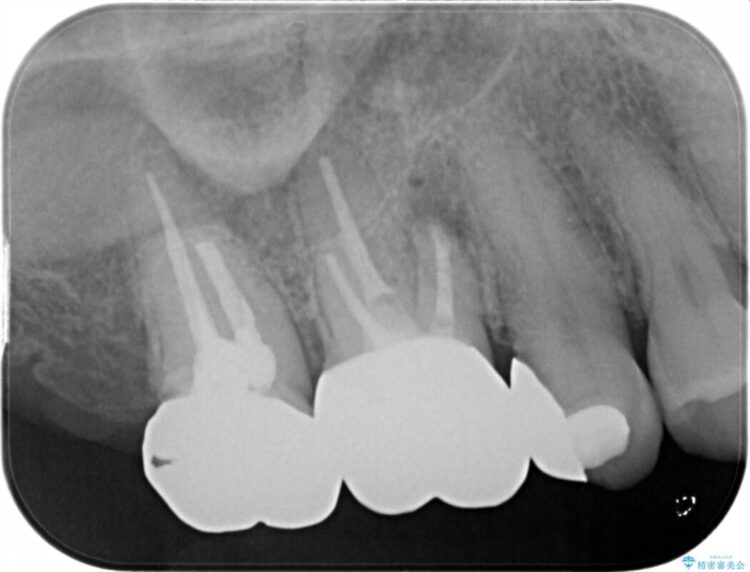

X線画像を診断すると、充填不良の根管の先に透過像が認められたため、再根管治療をご提案いたしました。

根管治療を再度行うことでフィステル(ニキビのようなできもの)は消失しました。

最終的にセラミッククラウンによる補綴治療を行いました。